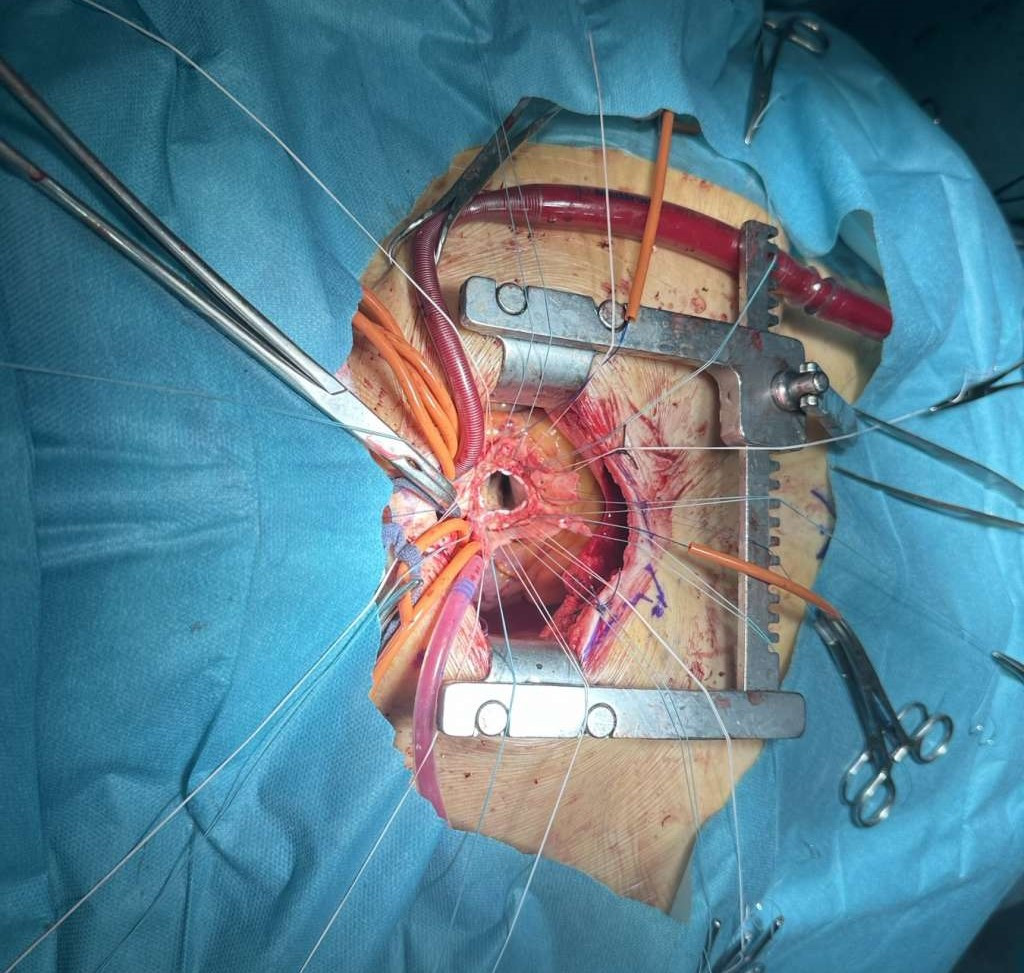

U Univerzitetskom kliničkom centru Tuzla uspješno izveden operativni zahvat zamjene aortne valvule i aneurizme početnog dijela aorte. Riječ je o minimalno invazivnoj metodi "Mini Bentall procedure".

Prema riječima vođe operativnog tima, prof. dr. med. sc. Haruna Avdagića radi se o vrlo složenoj hirurškoj proceduri koja zahtjeva izvrsnu educiranost čitavog tima i specifičnu pripremu pacijenta.

-Operativni zahvati ove vrste do sada nisu rađeni na Klinici za kardiovaskularnu hirurgiju UKC Tuzla, ali uz multidisciplinarni pristup i odličnu saradnju svih članova tima uspjeli smo izvesti Mini Bentall proceduru koja predstavlja vrlo složen operativni zahvat. Postoperativni tok protiče uredno i pacijentica je trenutno stabilnih vitalnih parametara, istakao je prof. dr. Avdagić.

Operativni tim Klinike za kardiovaskularnu hirurgiju činili su: prof. dr. med. sc. Harun Avdagić, subspecijalista kardiohirurgije i subspecijalista vaskularne hirurgija, uz asistenciju dr. Tarika Bakalovića i dr. Mirze Tokića, a anesteziolog je bila prof. dr. Alisa Krdžalić, anestetičar Haris Zulić, instrumentar Senad Brković i perfuzionista Rijad Imamović.